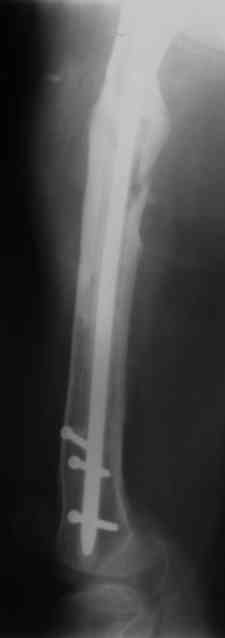

Для плечевой и большеберцовой кости - 10 мм, для бедренной - 12 мм.

Вчера наш пациент был на контрольном осмотре. Вроде все идет нормально. Рентгенограммы от 25 сентября 2007 г. (прошло 5 месяцев после операции) прилагаю.